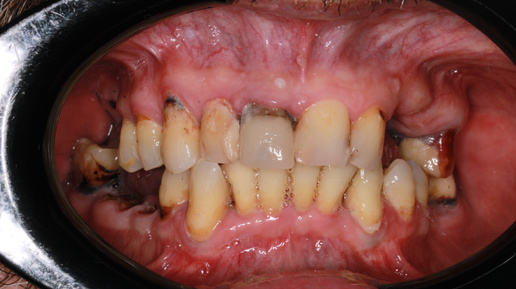

Сегодня показываем Вам успешный кейс пациента, который исполнил свою мечту об идеальной улыбке в клинике Санкт-Петербурга. Мы пообщались с врачами, участвующими в лечении и собрали для вас самые интересные детали о ходе лечения. В конце статьи вы узнаете, сколько стоило удалить все нездоровые зубы и установить новые. Мужчина. 49 лет Пациент обратился к нам в начале августа 2024 года со следующими жалобами: К сожалению, долгое время он не обращался к стоматологам из-за страха перед лечением. Госьков И...